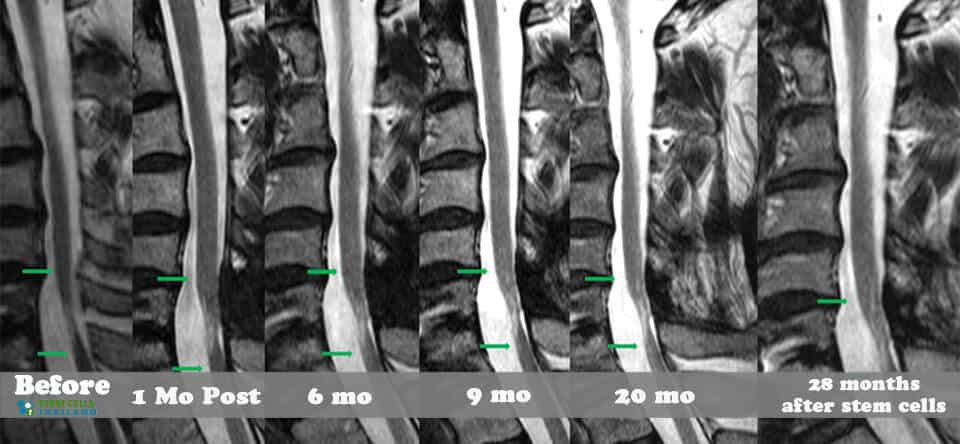

脊髓損傷的細(xì)胞療法側(cè)重于大腦和身體之間軸突的再生,這些軸突在事故發(fā)生后受到嚴(yán)重限制或不存在。我們針對(duì)脊髓損傷的干細(xì)胞移植可以幫助患者消除疼痛,恢復(fù)膀胱和腸道功能,恢復(fù)失去的感覺(jué),并再生內(nèi)臟運(yùn)動(dòng)神經(jīng)元,同時(shí)最大限度地減少其他問(wèn)題,例如損傷引起的痙攣或抑郁。傳統(tǒng)治療不解決再生問(wèn)題,而是側(cè)重于疼痛管理、康復(fù)和減少繼發(fā)性損傷。

基于細(xì)胞的治療采取更積極主動(dòng)的方法,通過(guò)刺激/增強(qiáng)受損細(xì)胞和組織的修復(fù)來(lái)促進(jìn)人類(lèi)的自然修復(fù)周期。修復(fù)受傷的脊髓和竹脊柱需要超越任何傳統(tǒng)技術(shù)來(lái)幫助您恢復(fù)部分/全部失去的功能。臨床試驗(yàn)表明,細(xì)胞更新和死亡是非常正常的,當(dāng)身體細(xì)胞受傷或老化時(shí),細(xì)胞會(huì)自然發(fā)生。這些死亡細(xì)胞通常被健康和受損的細(xì)胞包圍。我們針對(duì)坐骨神經(jīng)痛和椎管狹窄的治療方案通過(guò)利用神經(jīng)生長(zhǎng)因子和旁分泌信號(hào)傳導(dǎo)的靶向細(xì)胞因子療法,有助于促進(jìn)這些死亡或受傷細(xì)胞的愈合欺騙身體重新開(kāi)始愈合過(guò)程。

我們脊柱損傷治療中心的目標(biāo)是幫助以自然和安全的方式修復(fù)損傷。我們的治療是在細(xì)胞水平上進(jìn)行的,僅影響靠近影響點(diǎn)的區(qū)域。如果受傷時(shí)間不到兩年,積極的結(jié)果可能會(huì)非常顯著。對(duì)于那些患有老年損傷、創(chuàng)傷性腦損傷、嚴(yán)重椎間盤(pán)退變、股骨頭壞死、周?chē)窠?jīng)病變或脊髓性肌肉萎縮的人來(lái)說(shuō),隨著時(shí)間的推移,完全康復(fù)的機(jī)會(huì)變得更加困難。

組織、軟骨或韌帶的新?lián)p傷對(duì)干細(xì)胞治療的反應(yīng)要好得多。治療后的康復(fù)需要大量的奉獻(xiàn)和康復(fù)訓(xùn)練。初次治療后約2-3個(gè)月,身體改善明顯,且效果是永久性的。[2]